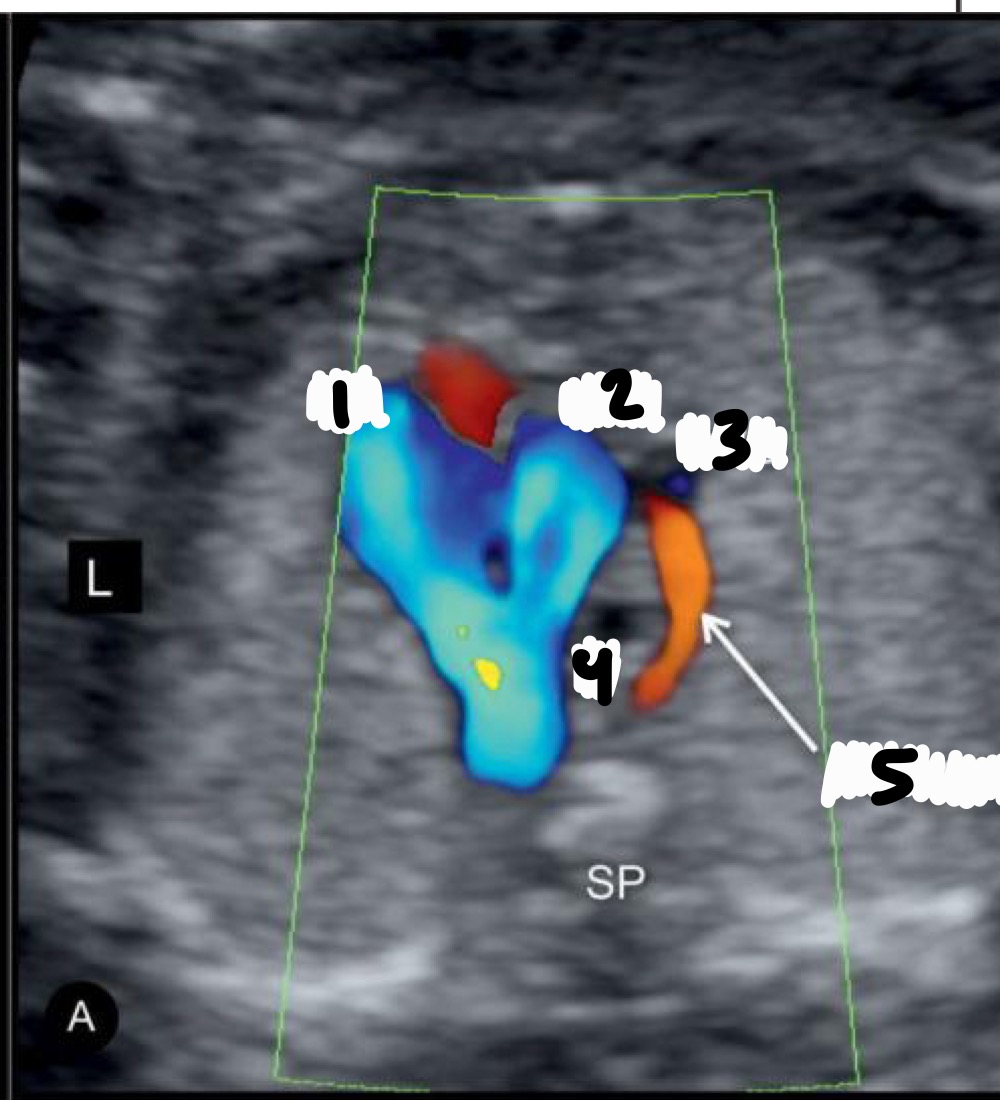

What view is this?

5 Chamber view

What additional structure is seen in the 5-chamber view

Aorta arising from the left ventricle

What is the purpose of the 5-chamber view

Evaluate aortic root and interventricular septum

Right ventricle

Left ventricle

Right atrium

Aorta

Left atrium

Descending aorta

What does LVOT stand for

Left ventricular outflow tract

What vessel arises from the left ventricle in LVOT

What is the "ballerina foot" sign associated with

LVOT view

What abnormality can be assessed in LVOT

Ventricular septal defect (VSD)

What does RVOT stand for

Right ventricular outflow tract

What vessel arises from the right ventricle

Pulmonary artery

What structures are seen after the pulmonary artery in RVOT

Ductus arteriosus and right pulmonary artery

What are common descriptors for RVOT appearance

Snail or walking man

MPA

Right pulmonary artery

Ductus Arteriosus

A= LVOT

B= RVOT